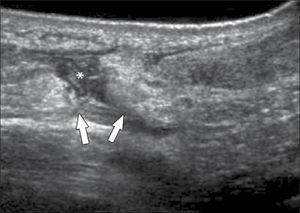

Ecografía de codoLas alteraciones más frecuentemente diagnosticadas en esta articulación son: Epicondilitis-codo del tenista (tendinopatía extensora), Epitrocleítis-epicondilitis medial- codo del golfista (tendinopatía flexora), derrame articular ya sea de origen inflamatorio o asociado a fracturas ocultas (figura 6), neuropatía cubital ya sea por atrapamiento o luxación, bursitis olecraneana (figura 7), tendinopatía tricipital, del biceps distal y su bursa, lesiones por elongación del ligamento colateral cubital, quistes/gangliones periarticulares, prominencias en rebordes óseos articulares, calcificaciones y entesopatía (14, 15).

Las indicaciones más habituales son: Tenosinovitis de De Quervain (tenosinovitis estenosante del compartimento 1 extensor), Tenosinovitis flexoras o extensoras en los distintos tendones (16) (figura 8), evaluación en pacientes con Síndrome de Túnel del carpo, para el aspecto del nervio mediano y la búsqueda de factores anatómicos que puedan estar condicionando el atrapamiento (tenosinovitis flexora en el túnel, quistes, variantes anatómicas, entre otras) (17), aumentos de volumen en estudio encontrándose principalmente quistes o gangliones (18), Derrame-Sinovitis en muñeca y carpo, ya sean post traumáticas o en enfermedades inflamatorias, donde además es necesaria la evaluación con Doppler Color de la vascularización sinovial.